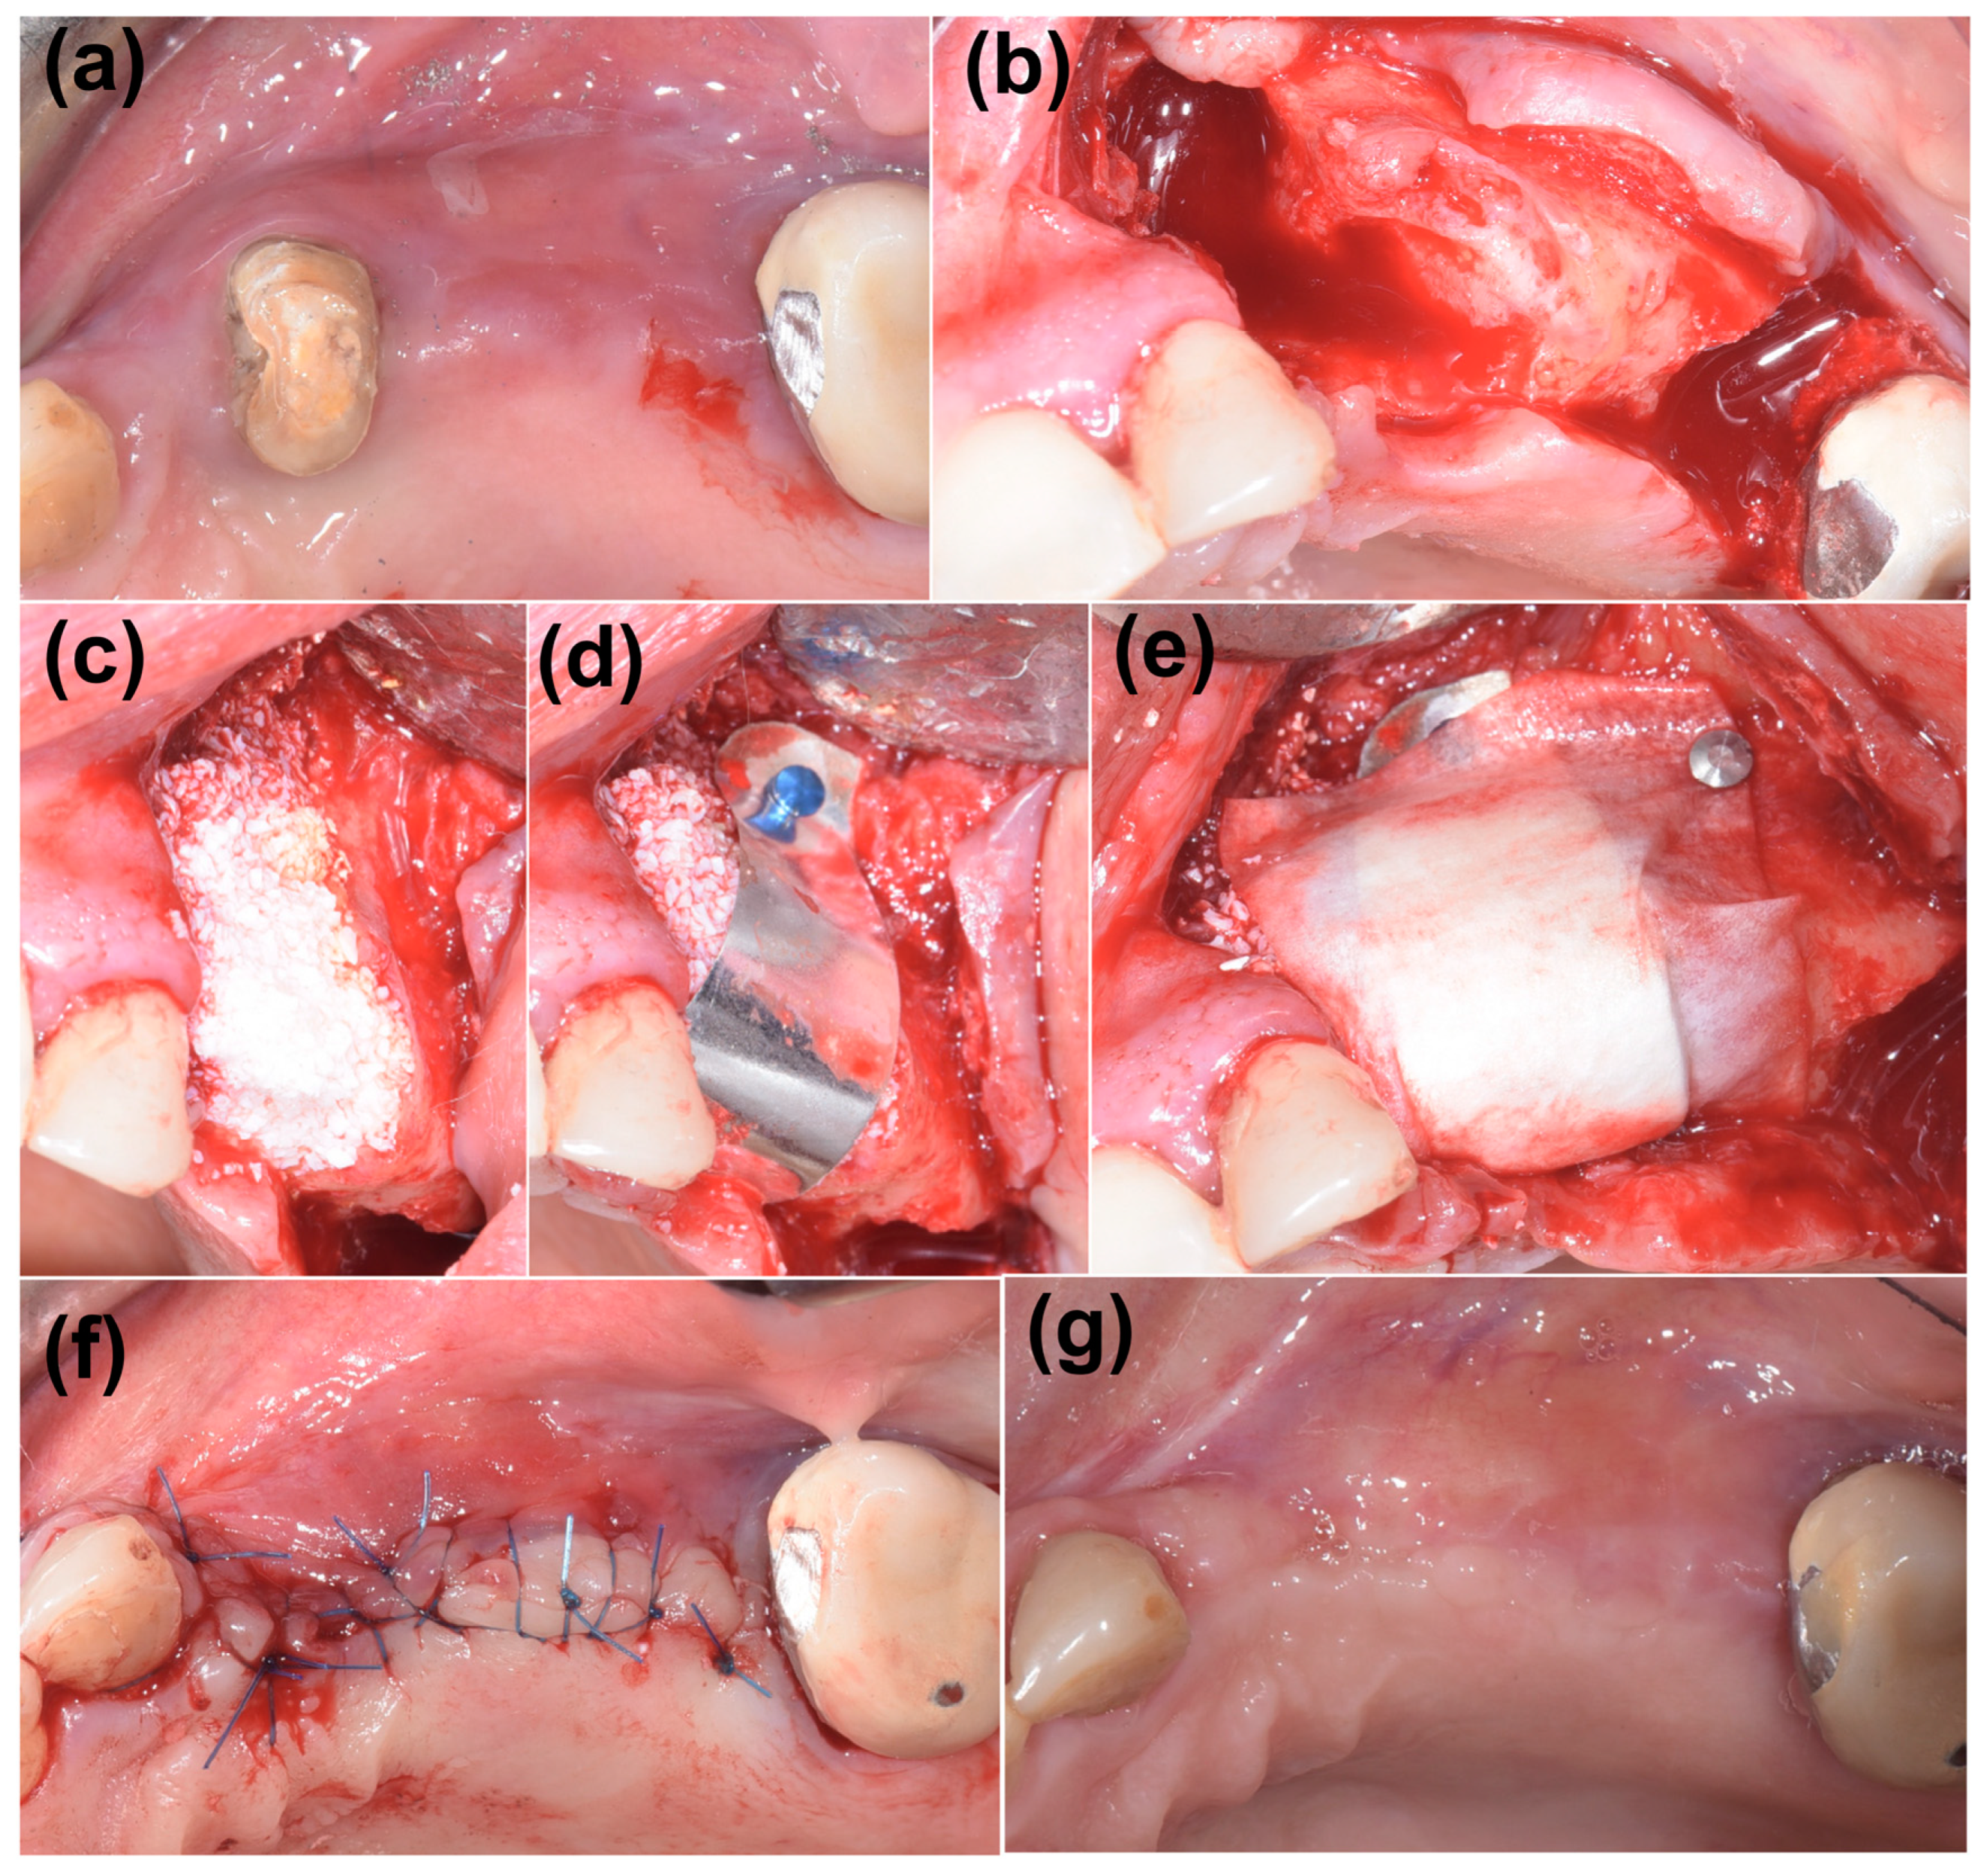

2. Case Presentation